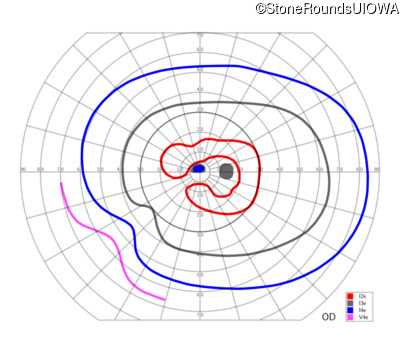

This 52 year old man had normal vision until his mid 30's when he began to have trouble distinguishing colors. the issuing 10 years he had a gradual loss of visual acuity accompanied by increasing photophobia.

| Age at visit: 58 years |